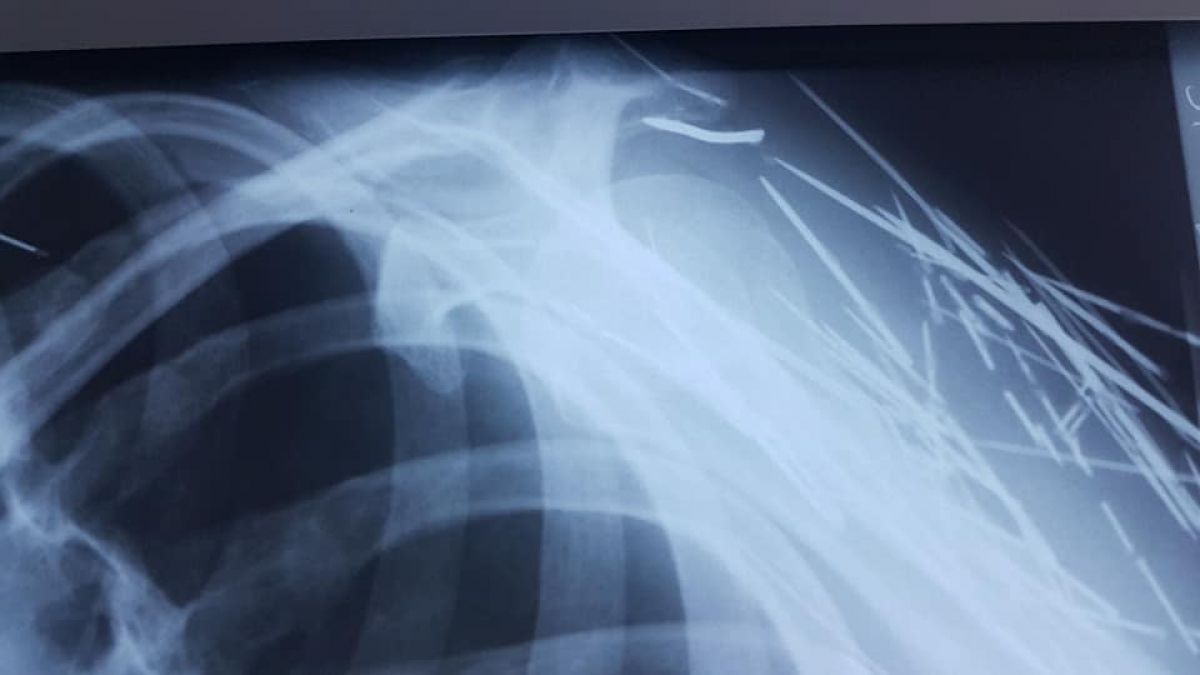

Ace, cuie și sârme au fost găsite în corpul unui pacient, imaginile fiind făcute publice de un medic din Botoșani. ”În 40 de ani de când mă învârt în ale medicinii nu am văzut așa ceva”, spune medicul Elena Cardaș, care a postat pe Facebook fotografiile, menționând că este vorba despre un pacient cu tulburări afective și psihice.

”Ce se mai poate găsi în corpul unui pacient. Ace, cuie, sârme. În 40 de ani de când mă învârt în ale medicinii nu am mai văzut așa ceva. Ca o precizare, este vorba de un pacient cu tulburări afective și psihice. Acele sunt de mult acolo, umăr, gât, axilă. Corpul le acceptă. Ce sa facă, săracul. Este o victimă”, a scris medicul Elena Cardaș.

Oamenii s-au arătat îngroziți de imaginile care însoțesc postarea. Fiind vorba despre persoane cu probleme psihice, manifestările de acest gen intră în sfera patologică. Potrivit celor precizate de medic, obiectele au fost introduse în corp de-a lungul vremii.

”Îi face plăcere când îl doare. Se automutilează ori de câte ori are ocazia”, a completat medicul Elena Cardaș.